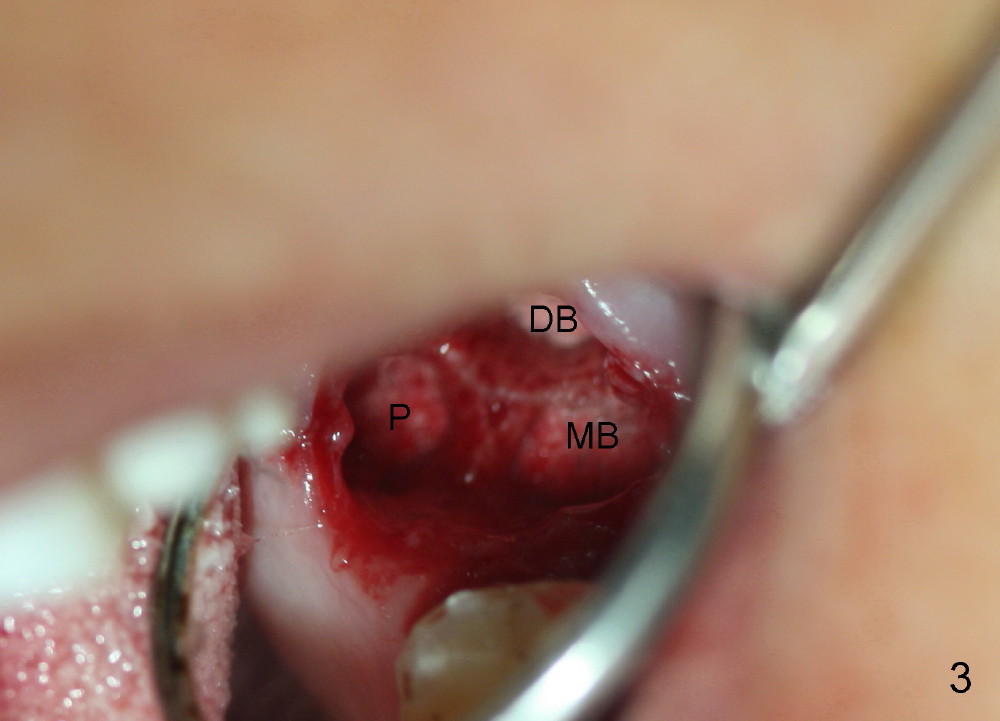

A 57-year-old lady presents for abscess buccal to the tooth #15 (Fig.1 A). Mesial and distal to the occlusal composite (Fig.2 C) is a crack line. In addition to long furcated roots, the upper border of the bone is not shown in this preop PA (arrow). Fig.3 is taken to show a thin septum surrounded by the mesiobuccal (MB), distobuccal (DB) and palatal (P) sockets (Fig.3). Osteotomy is initiated in the septum by 1.2 and 1.5 mm pilot drills, followed by 2,3,4 mm rounded tapered osteotomy at the depth of 17 mm. Nose blowing test is carried out after each step with negative result. Stability is achieved when a 4.5 mm tap is inserted at 17 mm, but the upper end of the tap is not visible (Fig.4,5). When a 5 mm tap is placed, stability is decreased, probably because the coronal end of the septum starts to break down (due to expansion). To re-gain stability, the 5 mm tap needs to go deeper. A 6 mm tap also achieves satisfactory stability at 20 mm. When the tap is removed, there is no air leakage. A 6x20 mm implant is placed with insertion torque > 60 Ncm; the upper end of the implant is still out of view in PA (Fig.6). Another problem is that the implant needs to go deeper to obtain sufficient occlusal clearance. The lower first molars and the 2nd premolars are missing. A panoramic X-ray has to be taken to show the apical end of the implant: ~ 3 mm into the sinus (Fig.7 ^). The maxillary tuberosity appears to grow downward (arrow). In other word, the tooth #15 appears to have been intruded due to overloading.